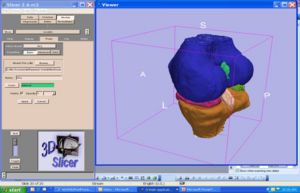

3D Slicer is a free open source software package distributed under a BSD style license. The majority of funding for the development of 3D slicer comes from a number of grants and contracts from the National Institutes of Health (see slicer acknowledgements for more information).

We invite you to provide information on how you are using 3D Slicer to produce peer-reviewed research. Information about the scientific impact of this tool is helpful in raising funding for the continued support of this tool.